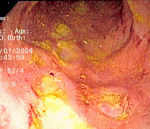

At the time of colonoscopy, biopsies of the colon are often taken in order to confirm the diagnosis. There are certain characteristic features of the pathology seen that point toward Crohn's disease. Crohn's disease shows a transmural pattern of inflammation, meaning that the inflammation may span the entire depth of the intestinal wall. Grossly, ulceration is an outcome seen in highly active disease. There is usually an abrupt transition between unaffected tissue and the ulcer. Under a microscope, biopsies of the affected colon may show mucosal inflammation. This inflammation is characterized by focal infiltration of neutrophils, a type of inflammatory cell, into the epithelium. This typically occurs in the area overlying lymphoid aggregates. These neutrophils, along with mononuclear cells, may infiltrate into the crypts leading to inflammation (crypititis) or abscess (crypt abscess). Granulomas, aggregates of macrophage derivatives known as giant cells, are found in 50% of cases and are most specific for Crohn's disease. The granulomas of Crohn's disease do not show "caseation", a cheese-like appearance on microscopic examination that is characteristic of granulomas associated with infections such as tuberculosis. Biopsies may also show chronic mucosal damage as evidenced by blunting of the intestinal villi, atypical branching of the crypts, and change in the tissue type ( metaplasia). One example of such metaplasia, Paneth cell metaplasia, involves development of Paneth cells (typically found in the small intestine) in other parts of the gastrointestinal system.